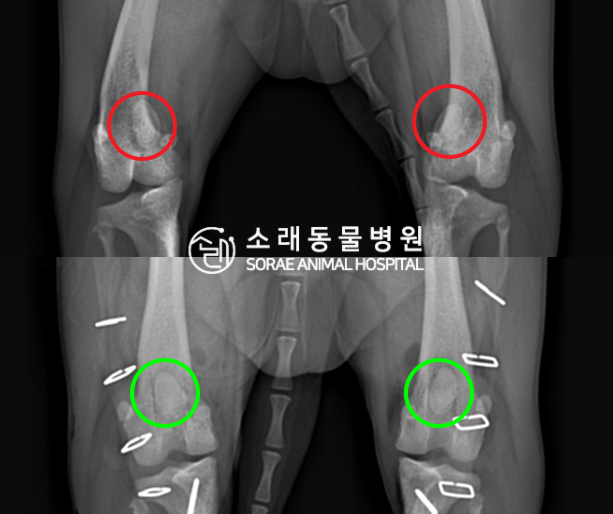

수술전과 수술후에 촬영한 구름이의 슬개골

방사선 사진입니다. 나란히 놓고 비교해보니

슬개골의 위치에 확연한 차이가 있는 것을

확인해 볼 수 있는데요. 내측으로 탈구되어 있던

슬개골이 원래 제자리인 활차구에 예쁘게

자리 잡고 있는 모습을 확인할 수 있었습니다.